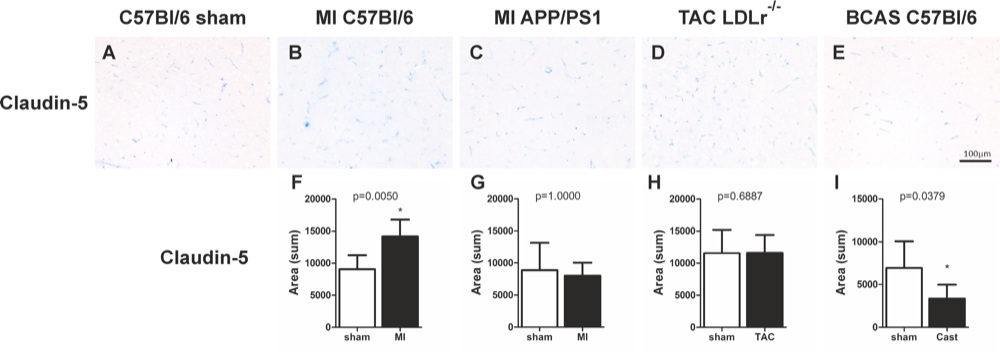

Chapter 6 Figure 5Representative cortical images of the tight junction marker claudin-5 (A-E) are shown of the different mouse models. Graphs of changes in cortical claudin-5 expression (F-I) 12 weeks after surgery are shown for the MI C57Bl/6 (F; n=4, 12), MI APP/PS1 (G; n=5, 9), TAC LDLr-/- (H; n=9, 13), BCAS C57Bl/6 (I; n=7, 7) mice. * p<0.05 is considered significant.